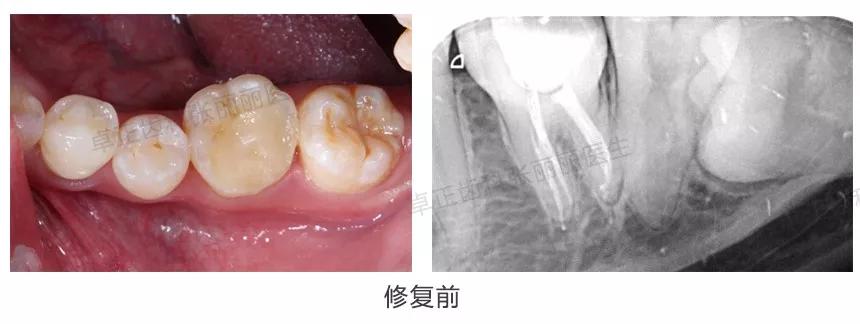

▍ 桩核冠

当后牙缺损面积大,剩余牙体组织不能为全冠提供固位力时,同样需要在根管内加桩来增加固位。